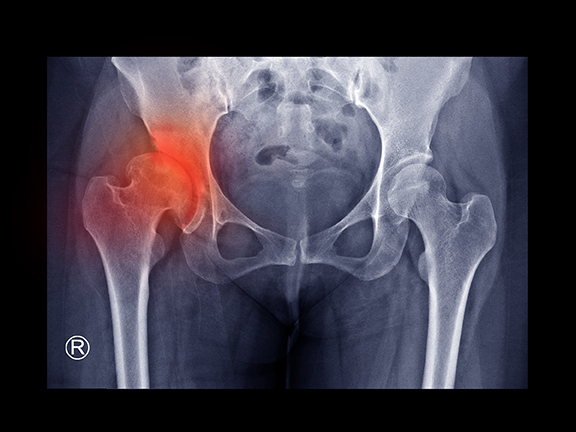

盤腿總是容易麻、下蹲好困難? 上下樓梯時經常覺得鼠蹊部與大腿外側疼痛?

家事做太多、過度勞動都有可能加速髖關節的退化,

天冷時這些痠痛、不適的感覺甚至會加劇,影響日常活動......。